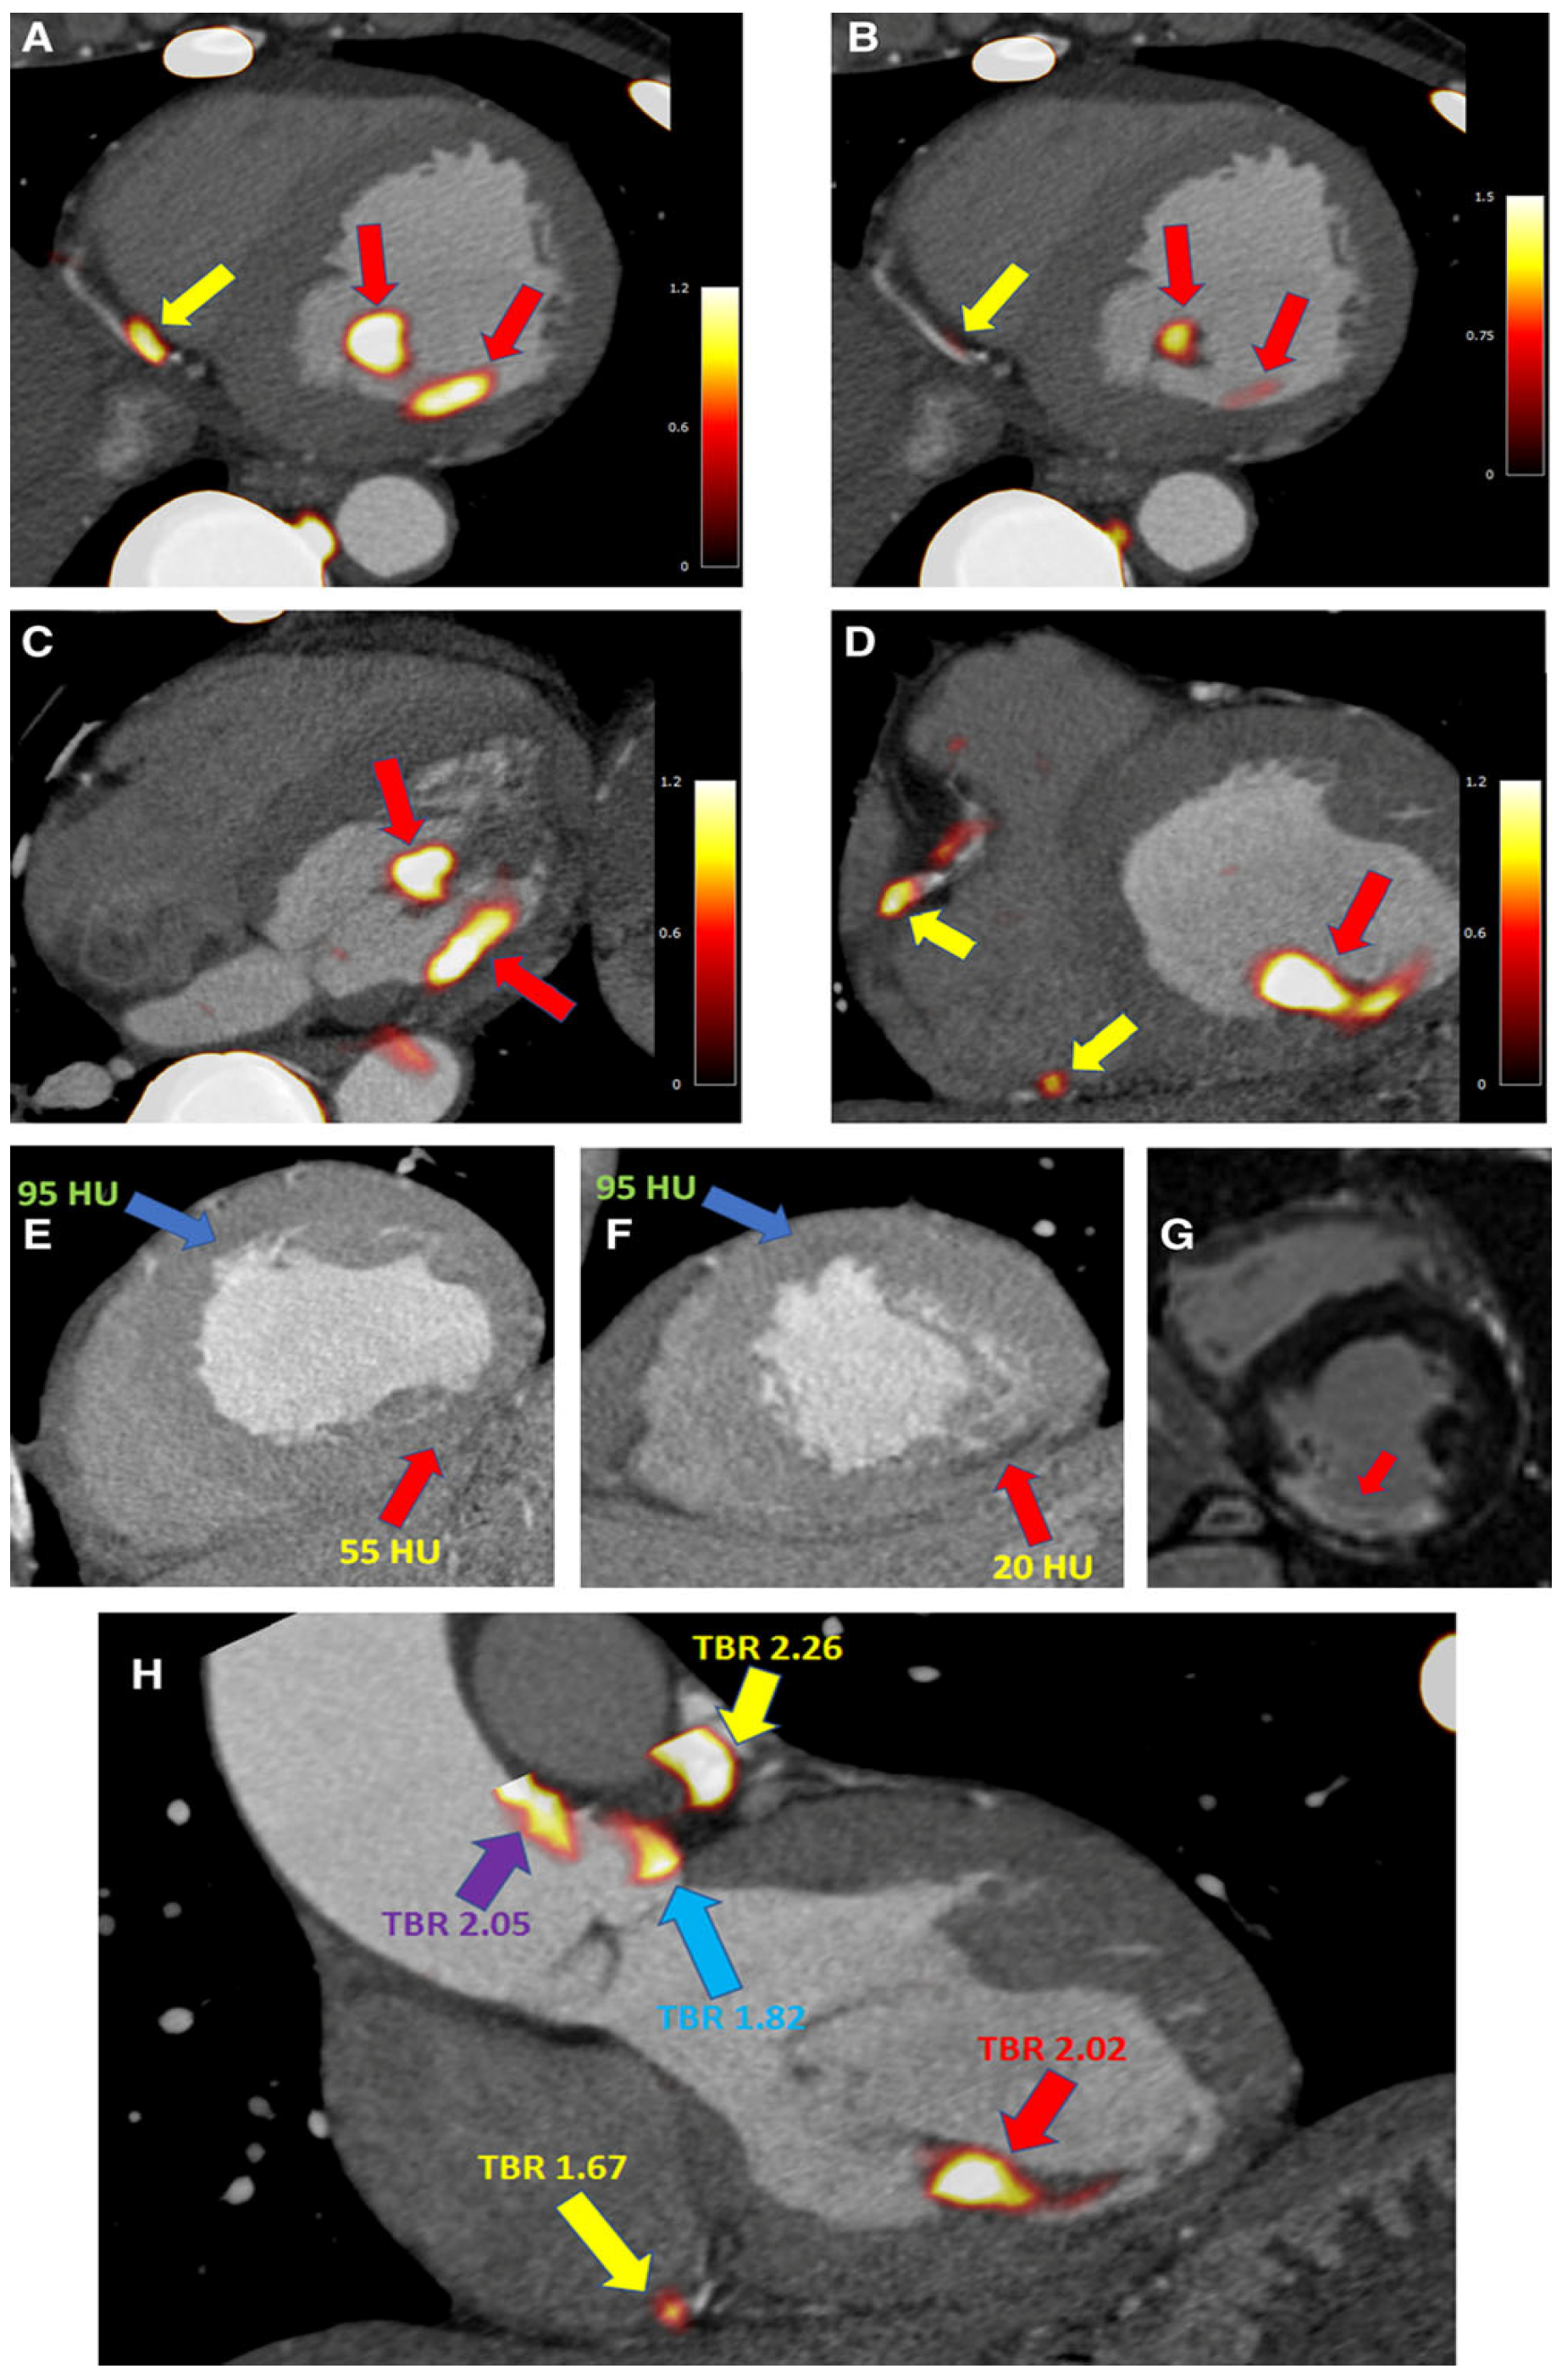

13. Metabolic Activity and Microcalcifications Visualization: 18F NaF